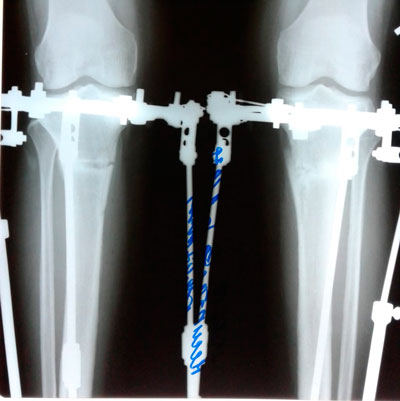

Дата операции - 05.03.2019г.

Дата снятия аппаратов - 26.06.2019г.

Срок сращения - 110 дней.